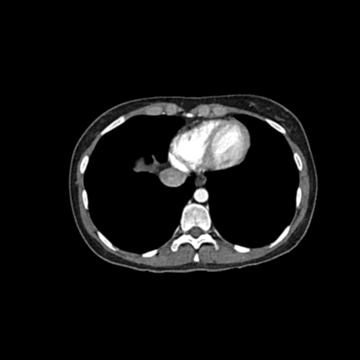

WEK53-01腹部模體,WEK53-01動脈期腹部模體,WEK53-01腹部模型模擬了動脈期的造影劑增強腹部。它覆蓋了第十一胸椎至第四腰椎(部分包括在內)。

該模型可用于 CT(包括 CBCT)以評估和優化成像性能和后處理應用,包括支持 AI 的應用。它也適用于培訓目的。

該模型提供了對軟組織和骨組織的詳細而逼真的模擬。空隙中填充著約-160HU的纖維素-聚合物復合材料。